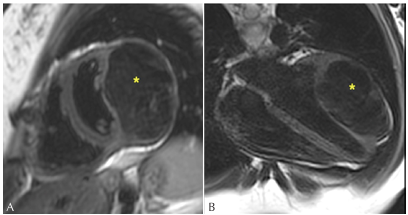

Figure 3: Short-axis showing an intramyocardial mass (*) with LGE of intense and homogeneous pattern. 2014 (A), 2017 (B), and 2018 (C).